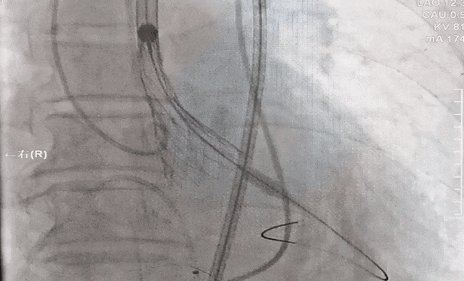

瓣膜释放过程

瓣膜完全释放,无瓣周漏